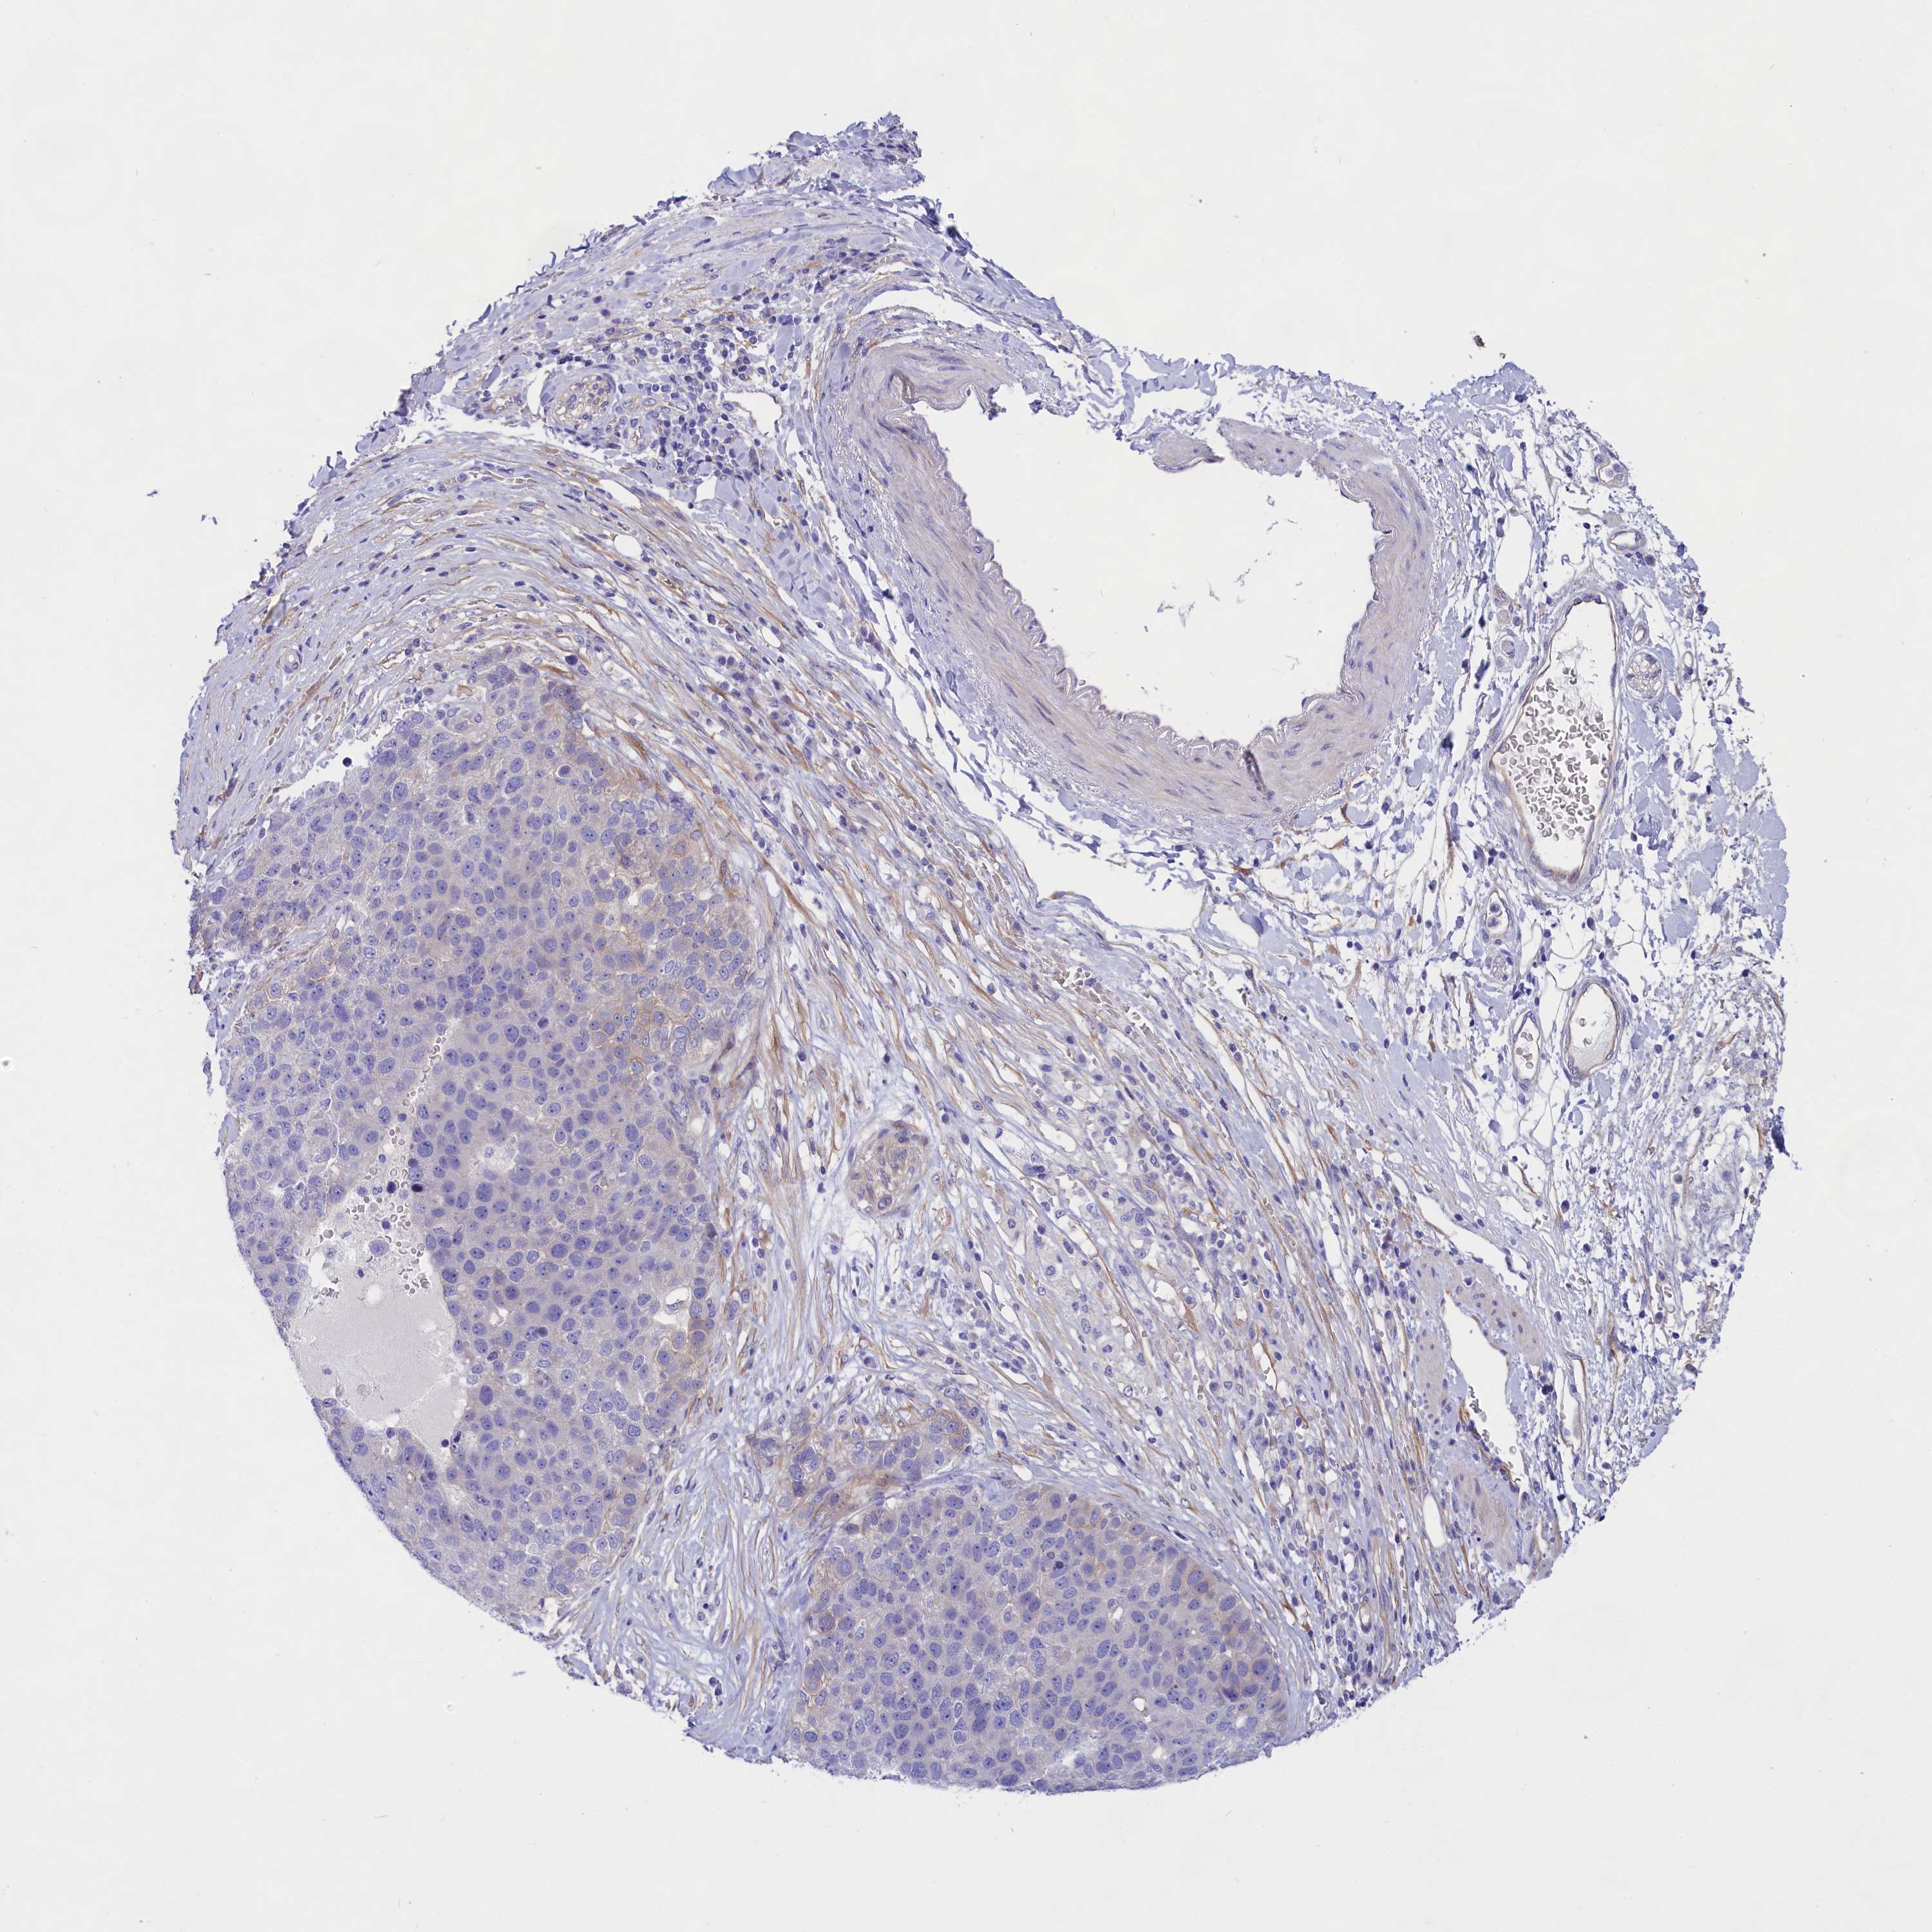

PANCREATIC CANCER - Protein expressioni

A mouse-over function shows sample information and annotation data. Click on an image to view it in a full screen mode. Samples can be filtered based on level of antibody staining by selecting one or several of the following categories: high, medium, low and not detected. The assay and annotation is described here.

Note that samples used for immunohistochemistry by the Human Protein Atlas do not correspond to samples in the TCGA dataset.

Antibody stainingi

Antibody staining in the annotated cell types in the current human tissue is reported as not detected, low, medium, or high, based on conventional immunohistochemistry profiling in selected tissues. This score is based on the combination of the staining intensity and fraction of stained cells.

Each image is clickable and will lead to virtual microscopy that enables deeper exploration of all samples and also displays staining intensity scores, fraction scores and subcellular localization as well as patient and tissue information for each sample.

Antibody HPA041231

Antibody HPA059883

Antibody CAB005016

Adenocarcinoma, NOS

Adenocarcinoma, metastatic, NOS